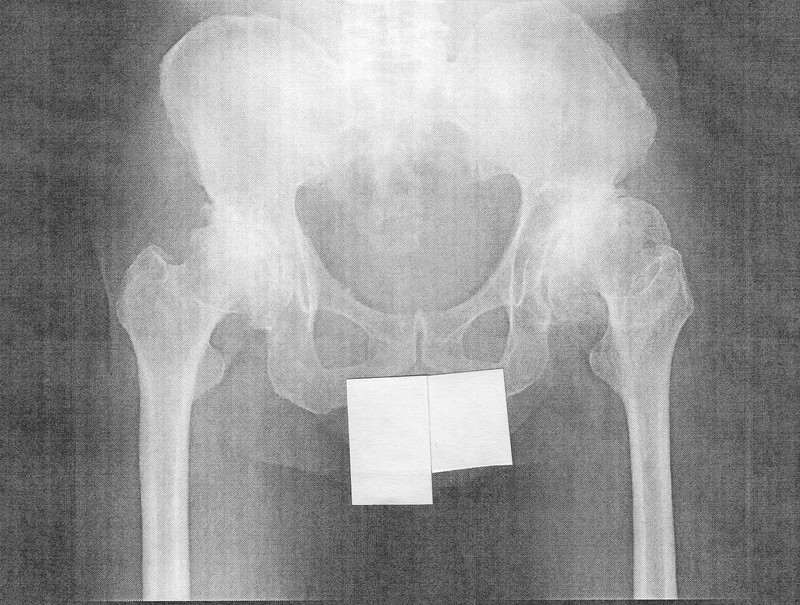

両 変形 性 股関節 症 情報 330